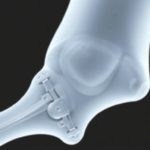

| Металлические биоматериалы | Титановые сплавы, иногда магниевые кандидаты | Высокая прочность, поддержка крупных дефектов, хорошая стабилизация | Риск вторичной операции по удалению, возможная коррозия, нужна пористость для остеоинтеграции | Порфирированные титановые импланты, пластины с пористыми поверхностями |

- Металлические импланты с пористыми поверхностями или покрытием из биоматериалов, которые ускоряют остеоинтеграцию.